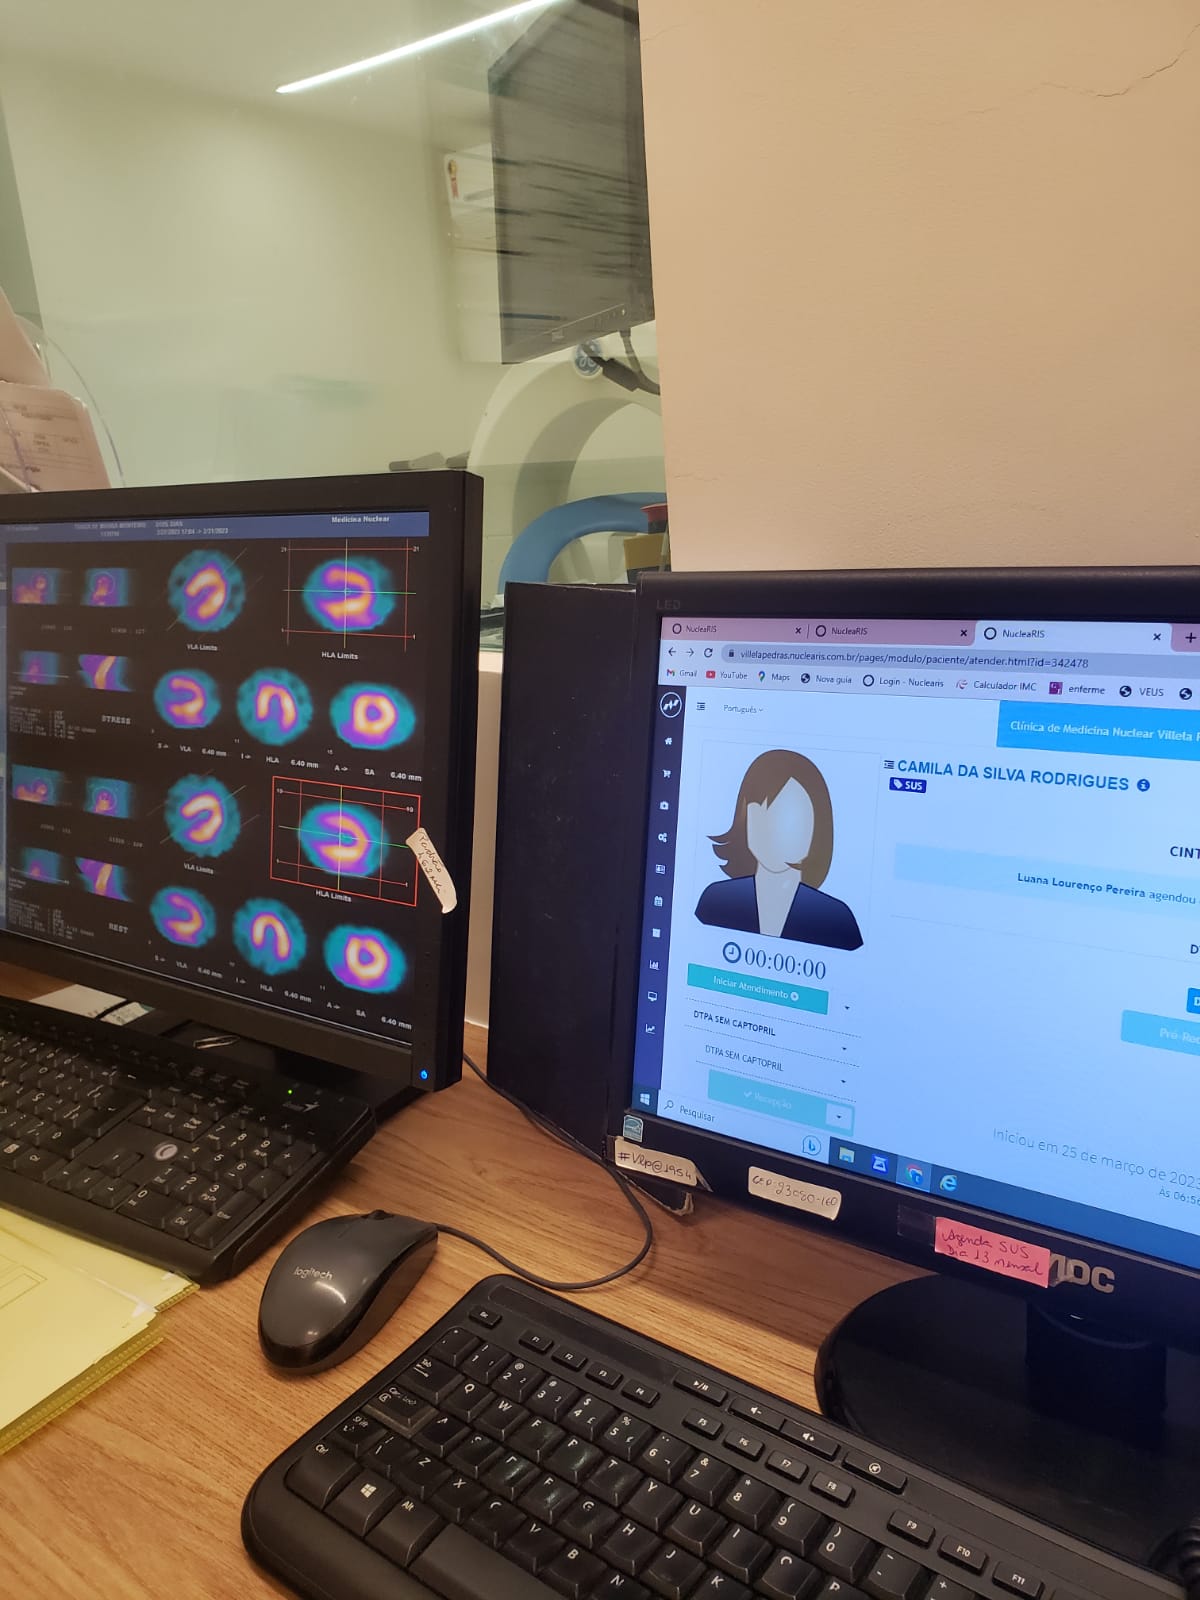

me chamo felipe, tenho 31 anos, trabalho na trabalho na área da saúde como cuidador no brasil, sou técnico de raio x e estudante de biomedicina no brasil